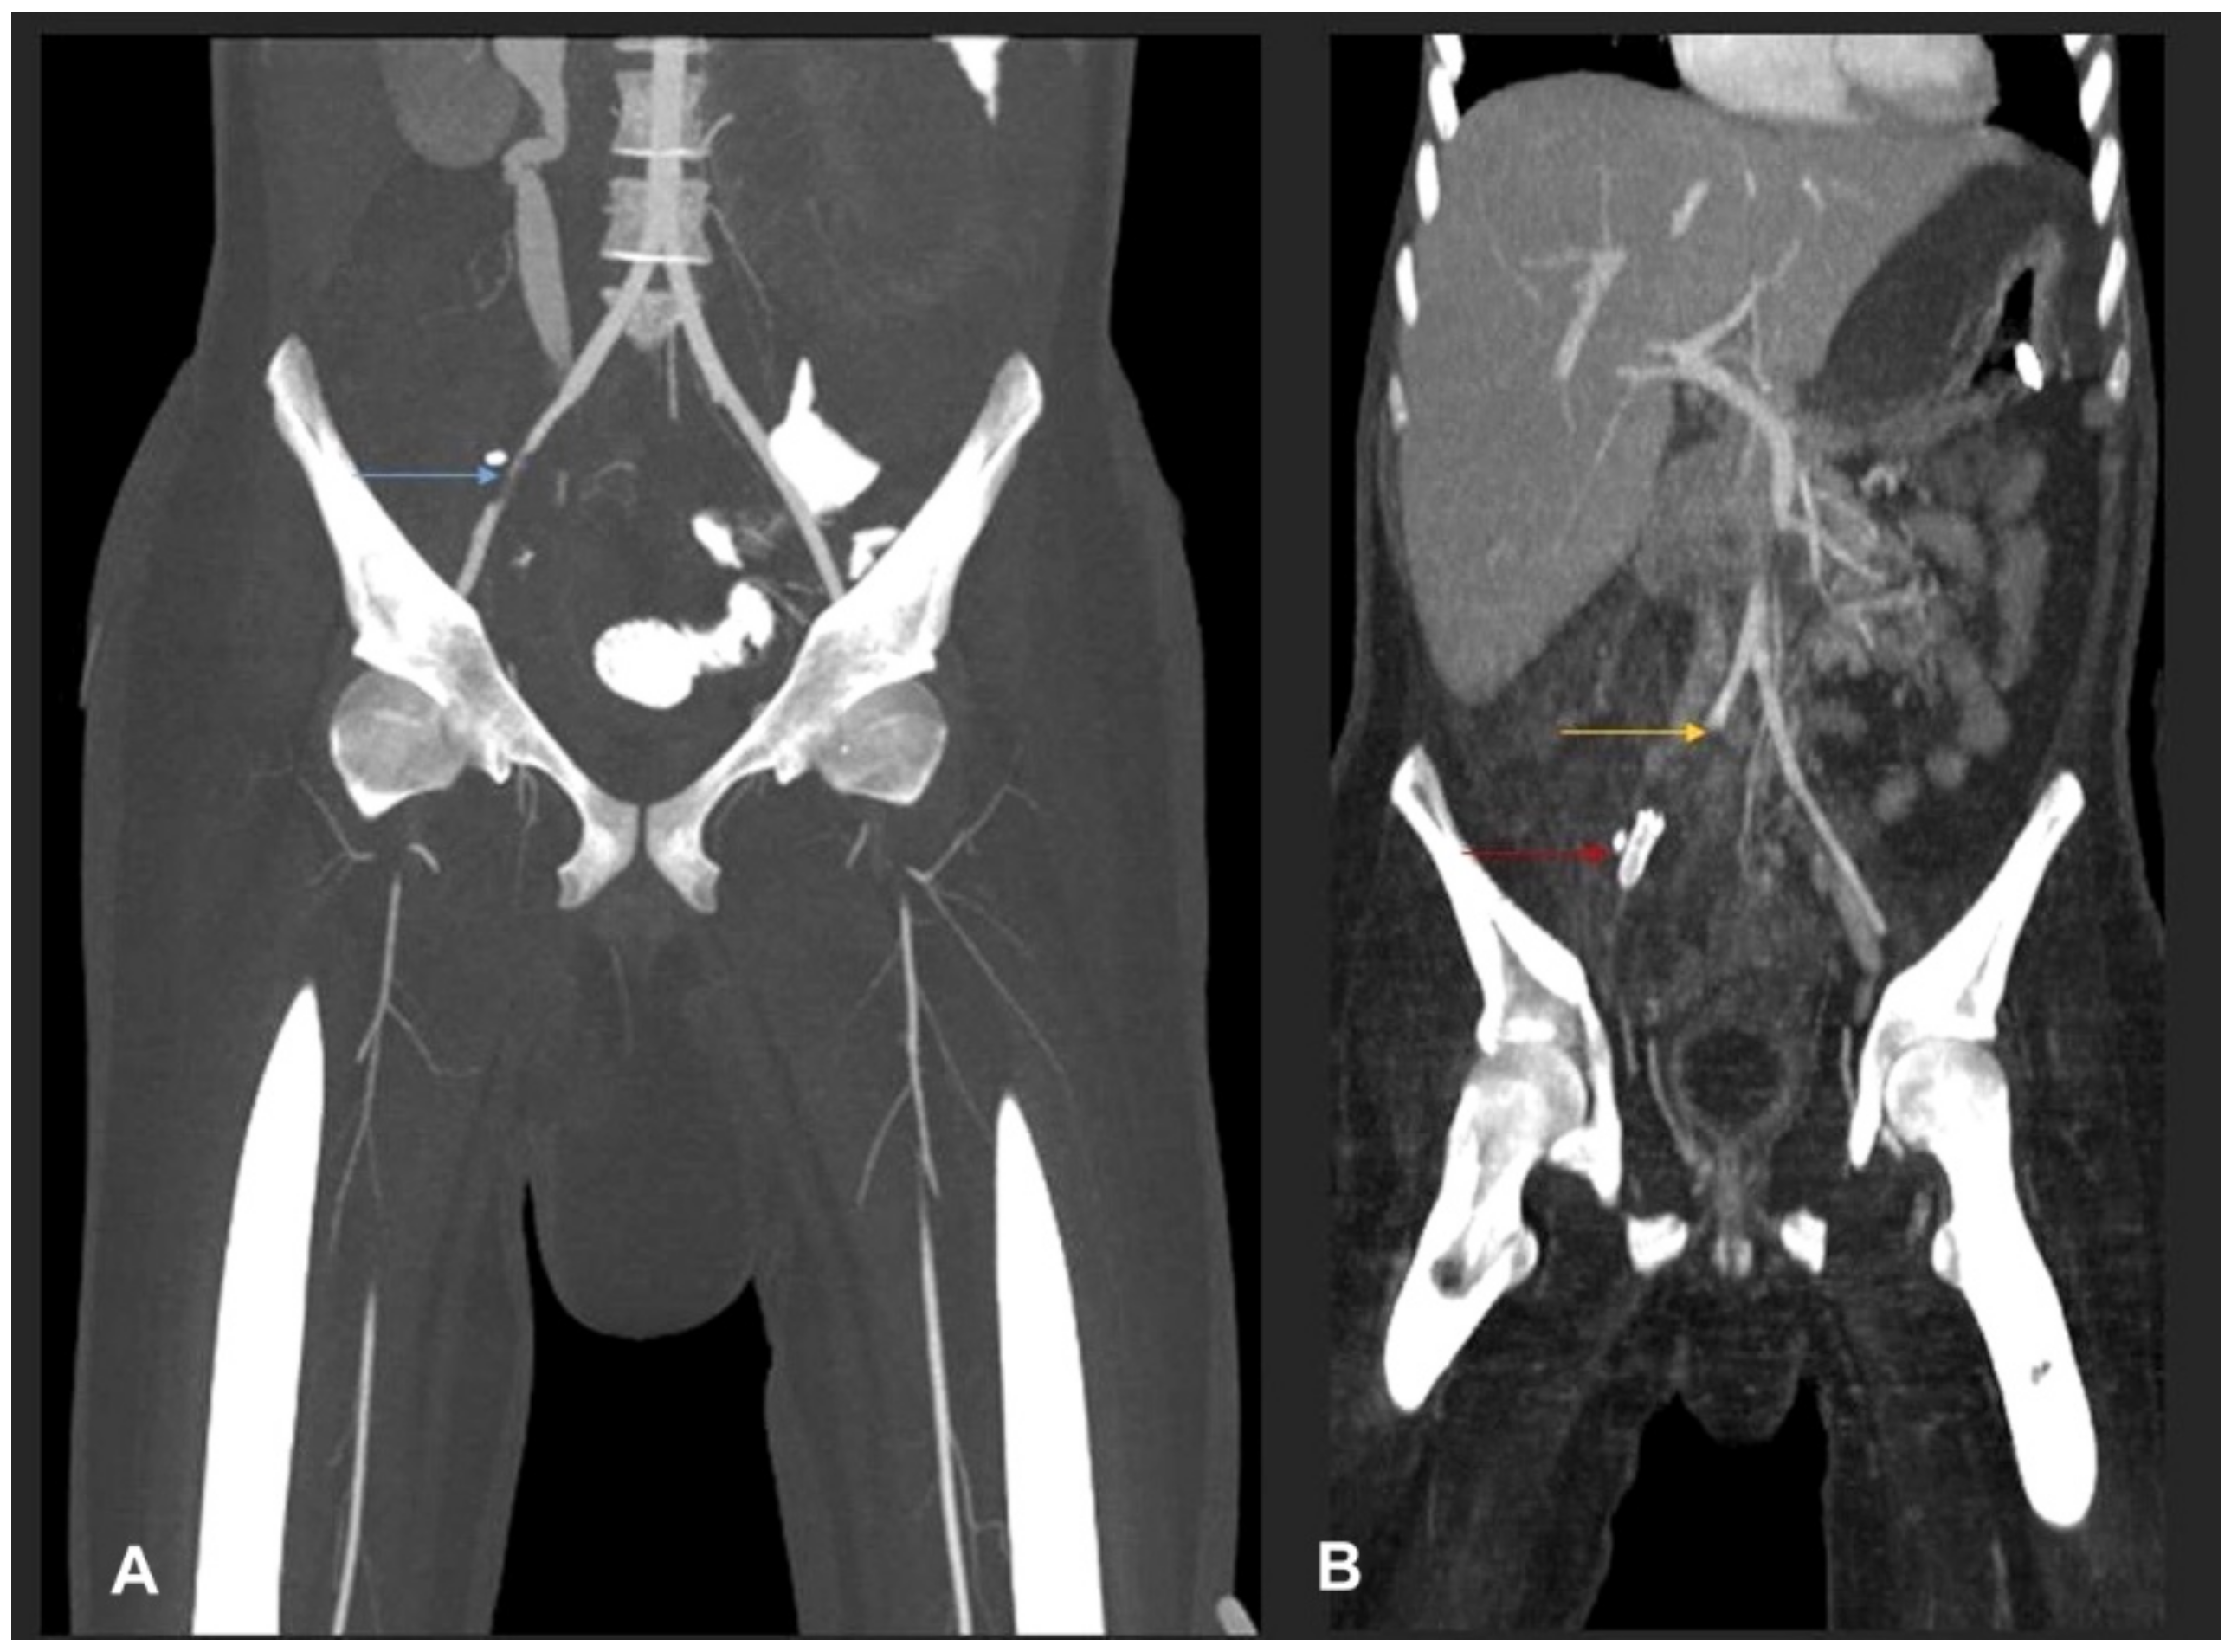

- Flicek, K.T.; Vikram, H.R.; De Petris, G.D.; Johnson, C.D. Abdominal imaging findings in gastrointestinal basidiobolomycosis. Abdom. Imaging 2015, 40, 246–250. [Google Scholar] [CrossRef]